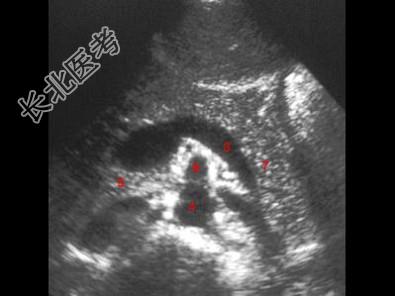

- 单项选择题图示6所指部位为 ( )

A、腹主动脉

B、肠系膜上静脉

C、脾静脉

D、肠系膜上动脉

E、胰尾